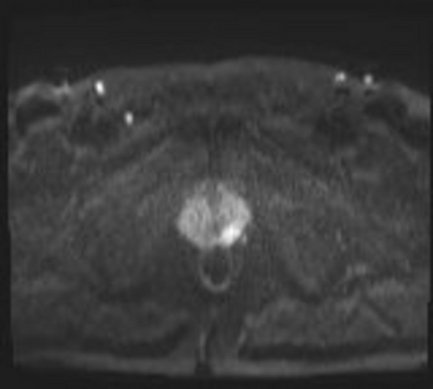

Multiparametrische MRT der Prostata

Die multiparametrische MRT der Prostata (mpMRT) dient der Erkennung von Veränderungen, die verdächtig auf das Vorliegen eines Prostatakarzinoms sind. Sie kann als Erstuntersuchung vor einer geplanten Biopsie (Gewebeentnahme) durchgeführt werden. Zusätzlich zur systematischen Biopsie können verdächtige Areale so gezielt biopsiert werden. Weiterhin ist sie eine wertvolle Untersuchung im Rahmen der „Active surveillance“ (aktive Überwachung) bei bekanntem Prostatakarzinom mit niedrigem Risiko. Die mpMRT hat dementsprechend in die aktuelle Version (Mai 2019) der „Interdisziplinären Leitlinie der Qualität Q3 zur Früherkennung, Diagnose und Therapie der verschiedenen Stadien des Prostatakarzinoms“ Einzug gehalten.